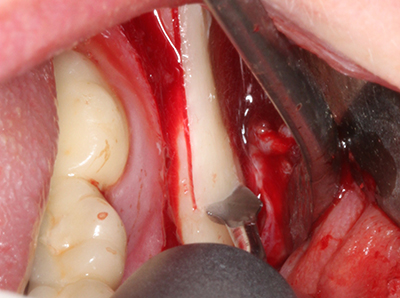

Quando le procedure chirurgiche vengono eseguite sull'osso nelle immediate vicinanze di strutture sensibili, come vasi sanguigni o nervi, gli strumenti rotanti pongono un rischio significativo di lesione iatrogena. I dispositivi piezoelettrici possono essere utili per la preparazione delle coperture ossee e la rimozione del tessuto duro in prossimità dei nervi, in particolare per la loro esposizione dopo una lesione iatrogena, ma anche durante la lateralizzazione dei nervi per le procedure di resezione e ricostruzione o il posizionamento di impianti (figg. 17-20). Il contatto leggero tra puntina piezoelettrica e nervo non causa generalmente danni, ma se si procede senza prestare attenzione con movimenti a sega o raccordi con residui di substrati ossei possono verificarsi danni al nervo temporanei o anche permanenti. Il rischio di danno, tuttavia, è considerato sostanzialmente inferiore al rischio presente utilizzando seghe o frese (Pereira, Gealh et al. 2014).

Indicazione: terapia parodontale